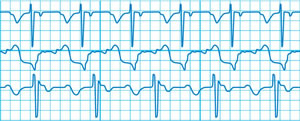

An echocardiogram, known also as a cardiac ECHO or ECHO, is a widely used, non-invasive cardiac diagnostic test. This quick, highly accurate test is relatively inexpensive and uses ultrasound to create two- and three-dimensional images of a patient's heart, allowing doctors to assess the size and shape of the heart, the heart's pumping capacity, any tissue damage or abnormalities, and much more. By performing and properly reading an ECHO, doctors can determine whether chest pain or other symptoms are related to heart disease and can then decide on the best course of treatment.